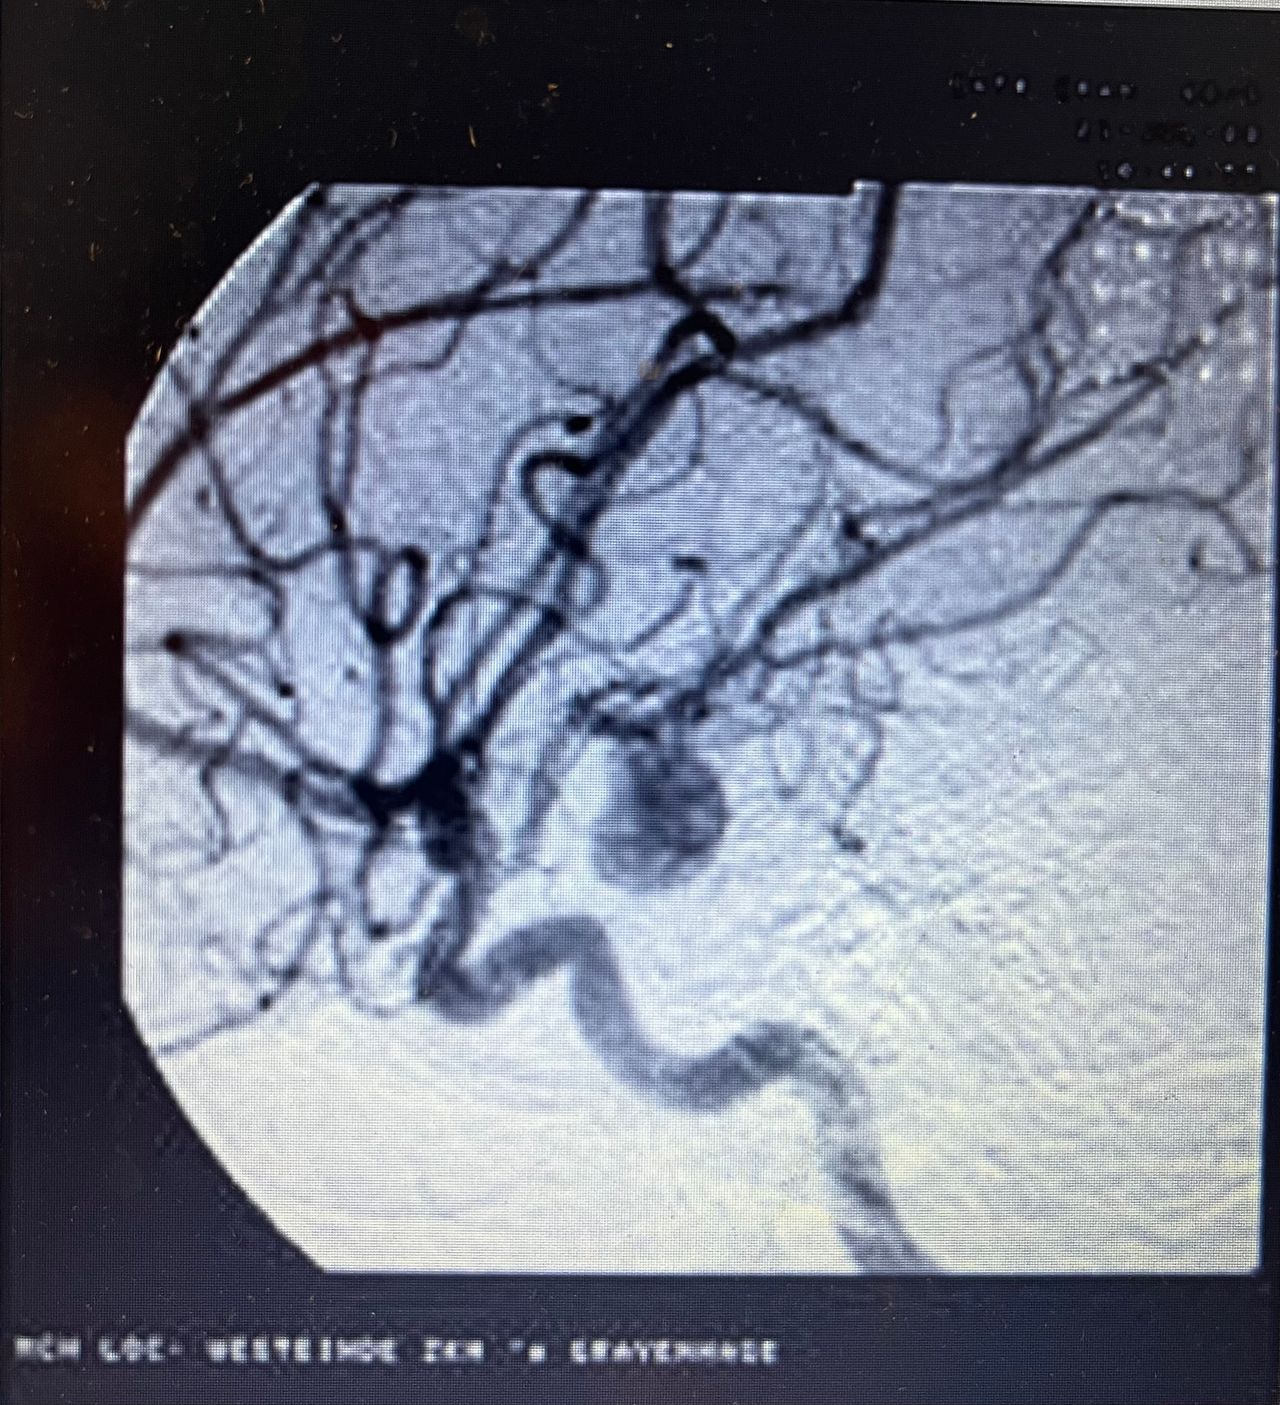

Foto e video